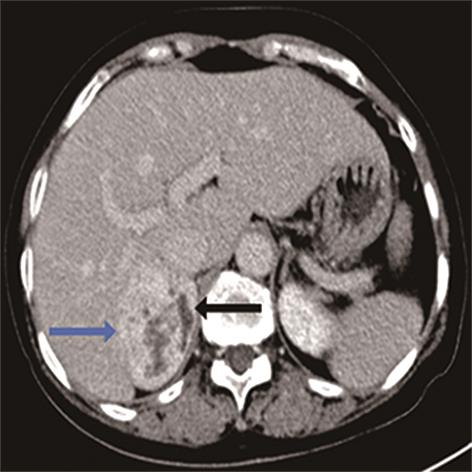

• 嗜铬细胞瘤及副神经节瘤不同生化表型的CT征象对比研究

2024, 49(2):203-209. DOI: 10.13406/j.cnki.cyxb.003433

摘要 (51) HTML (33) PDF 3.10 M (96) 评论 (0) 收藏

摘要:目的 分析生化阴性嗜铬细胞瘤及副神经节瘤(pheochromocytomas and paragangliomas,PPGLs)的电子计算机断层扫描(computed tomography,CT)征象是否有别于生化阳性PPGLs,同时了解生化阳性PPGLs不同表型的CT征象是否存在差异。方法 回顾性分析131例PPGLs患者的术前腹部增强CT图像,包括肿瘤位置、大小、形态、囊变坏死、液-液分层、钙化、向心结节状强化、肿瘤内粗大血管、强化包膜、绝对廓清率及相对廓清率。根据生化水平,将患者分为生化阳性组和阴性组,阳性组进一步分为去甲肾上腺素型、肾上腺素型及多巴胺型。比较各组及各表型间的CT征象差异。结果 相较于生化阴性组,阳性组PPGLs更大(Z=-2.064,P=0.039)、囊变坏死(χ2=6.610,P=0.010)及向心结节状强化(χ2=3.909,P=0.048)的比例更高;相较于去甲肾上腺素型,肾上腺素型PPGLs更大(Z=-2.036,P=0.042)、强化包膜比例更高(χ2=7.242,P=0.007)。结论 肿瘤大小、囊变坏死及向心结节状强化的CT征象有助于术前诊断生化阴性PPGLs,肿瘤大小及强化包膜有助于解释去甲肾上腺素型及肾上腺素型PPGLs不同临床表现产生的机制。